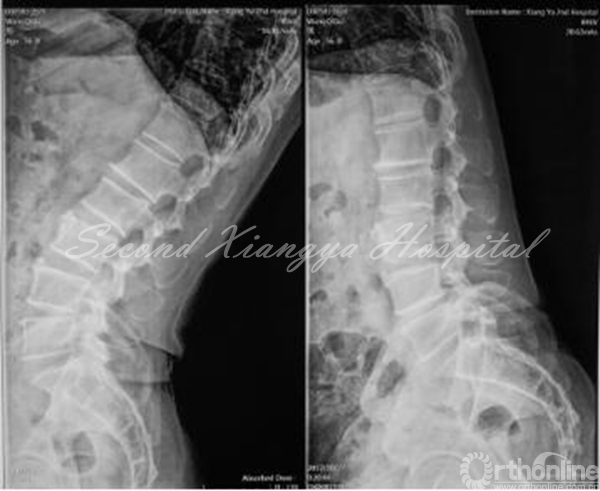

MRI:L4/5椎间盘右侧突出,非游离,无钙化,伴侧隐窝狭窄。

MRI-T2、MRI-T1